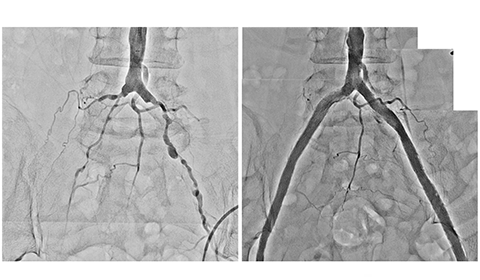

医師が PAD を疑う場合、通常は足首上腕指数検査を使用して診断を下すことができます。この検査では、足首と腕の血圧レベルを比較します。腕と比較して足首の血圧が低い場合は、PAD の兆候である可能性があります。